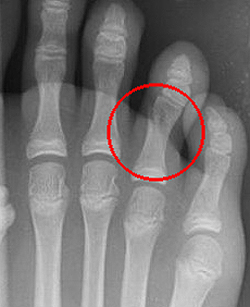

Переломы фаланг пальцев стопы

Эта разновидность переломов костей стопы, как правило, возникает при прямом воздействии травмирующей силы (падение тяжести, удар по пальцам). Переломы средней и ногтевой фаланг пальцев в последующем не нарушают функцию стопы. Неправильное сращение переломов основных фаланг может приводить к развитию посттравматических артрозов плюснефаланговых суставов, ограничению подвижности и болям при ходьбе.

Травмированный палец синюшен, отечен, резко болезненен при движениях, ощупывании и осевой нагрузке. Переломы ногтевой фаланги часто сопровождаются образованием подногтевой гематомы. Для подтверждения переломов фаланг выполняют рентгенограммы в 2-х проекциях.

При переломах фаланг пальцев стопы без смещения накладывают заднюю гипсовую шину. При смещении отломков выполняют закрытую репозицию. Костные фрагменты фиксируют спицами. При переломах ногтевой фаланги без смещения возможна иммобилизация с использованием лейкопластырной повязки. Срок фиксации зависит от тяжести перелома и составляет от 4 до 6 недель.

Переломы пальцев стопы

Обычно переломы пальцев возникают вследствие падения тяжелых предметов, поэтому нередко бывают открытыми либо сопровождаются выраженной травмой мягких тканей. Повреждения диафиза легко распознаются: появляется кровоизлияние, отек и боль, нарушается функция, отмечается положительный симптом осевой нагрузки. При эпифизеолизах без смещения симптомы могут напоминать ушиб, при эпифизеолизах со смещением – вывих фаланги. Диагноз помогает установить рентгенография.